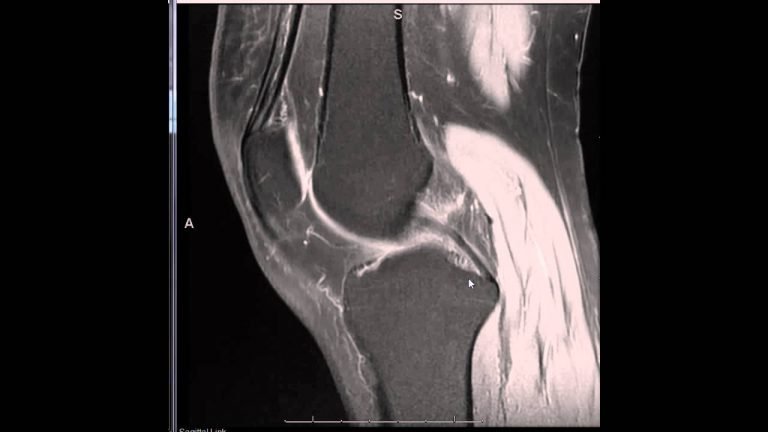

Reading MRI is always interesting and challenging to the medico persons. Not only for the medical person,...